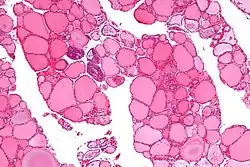

Tiroglobulina ou tireoglobulina é uma proteína dimérica produzida pelas células foliculares e utilizada na totalidade dentro da glândula tireoide. Formam coloides no centro dos folículos da tireoide. É usado na produção de tri-iodotironina (T3) e tetraiodotironina (T4).